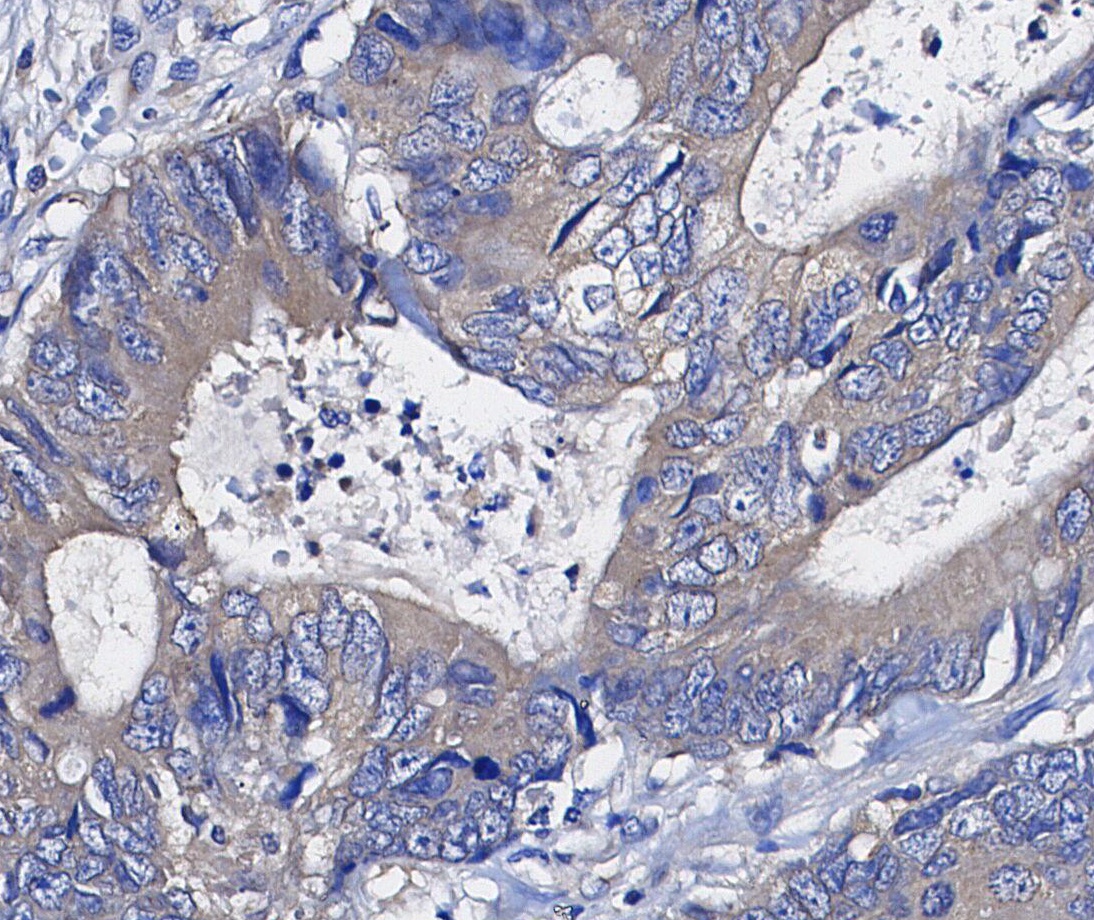

• Immunohistochemical analysis of formalin fixed paraffin embedded human Colorectal cancer tissue with F1132 at 1/200 dilution.